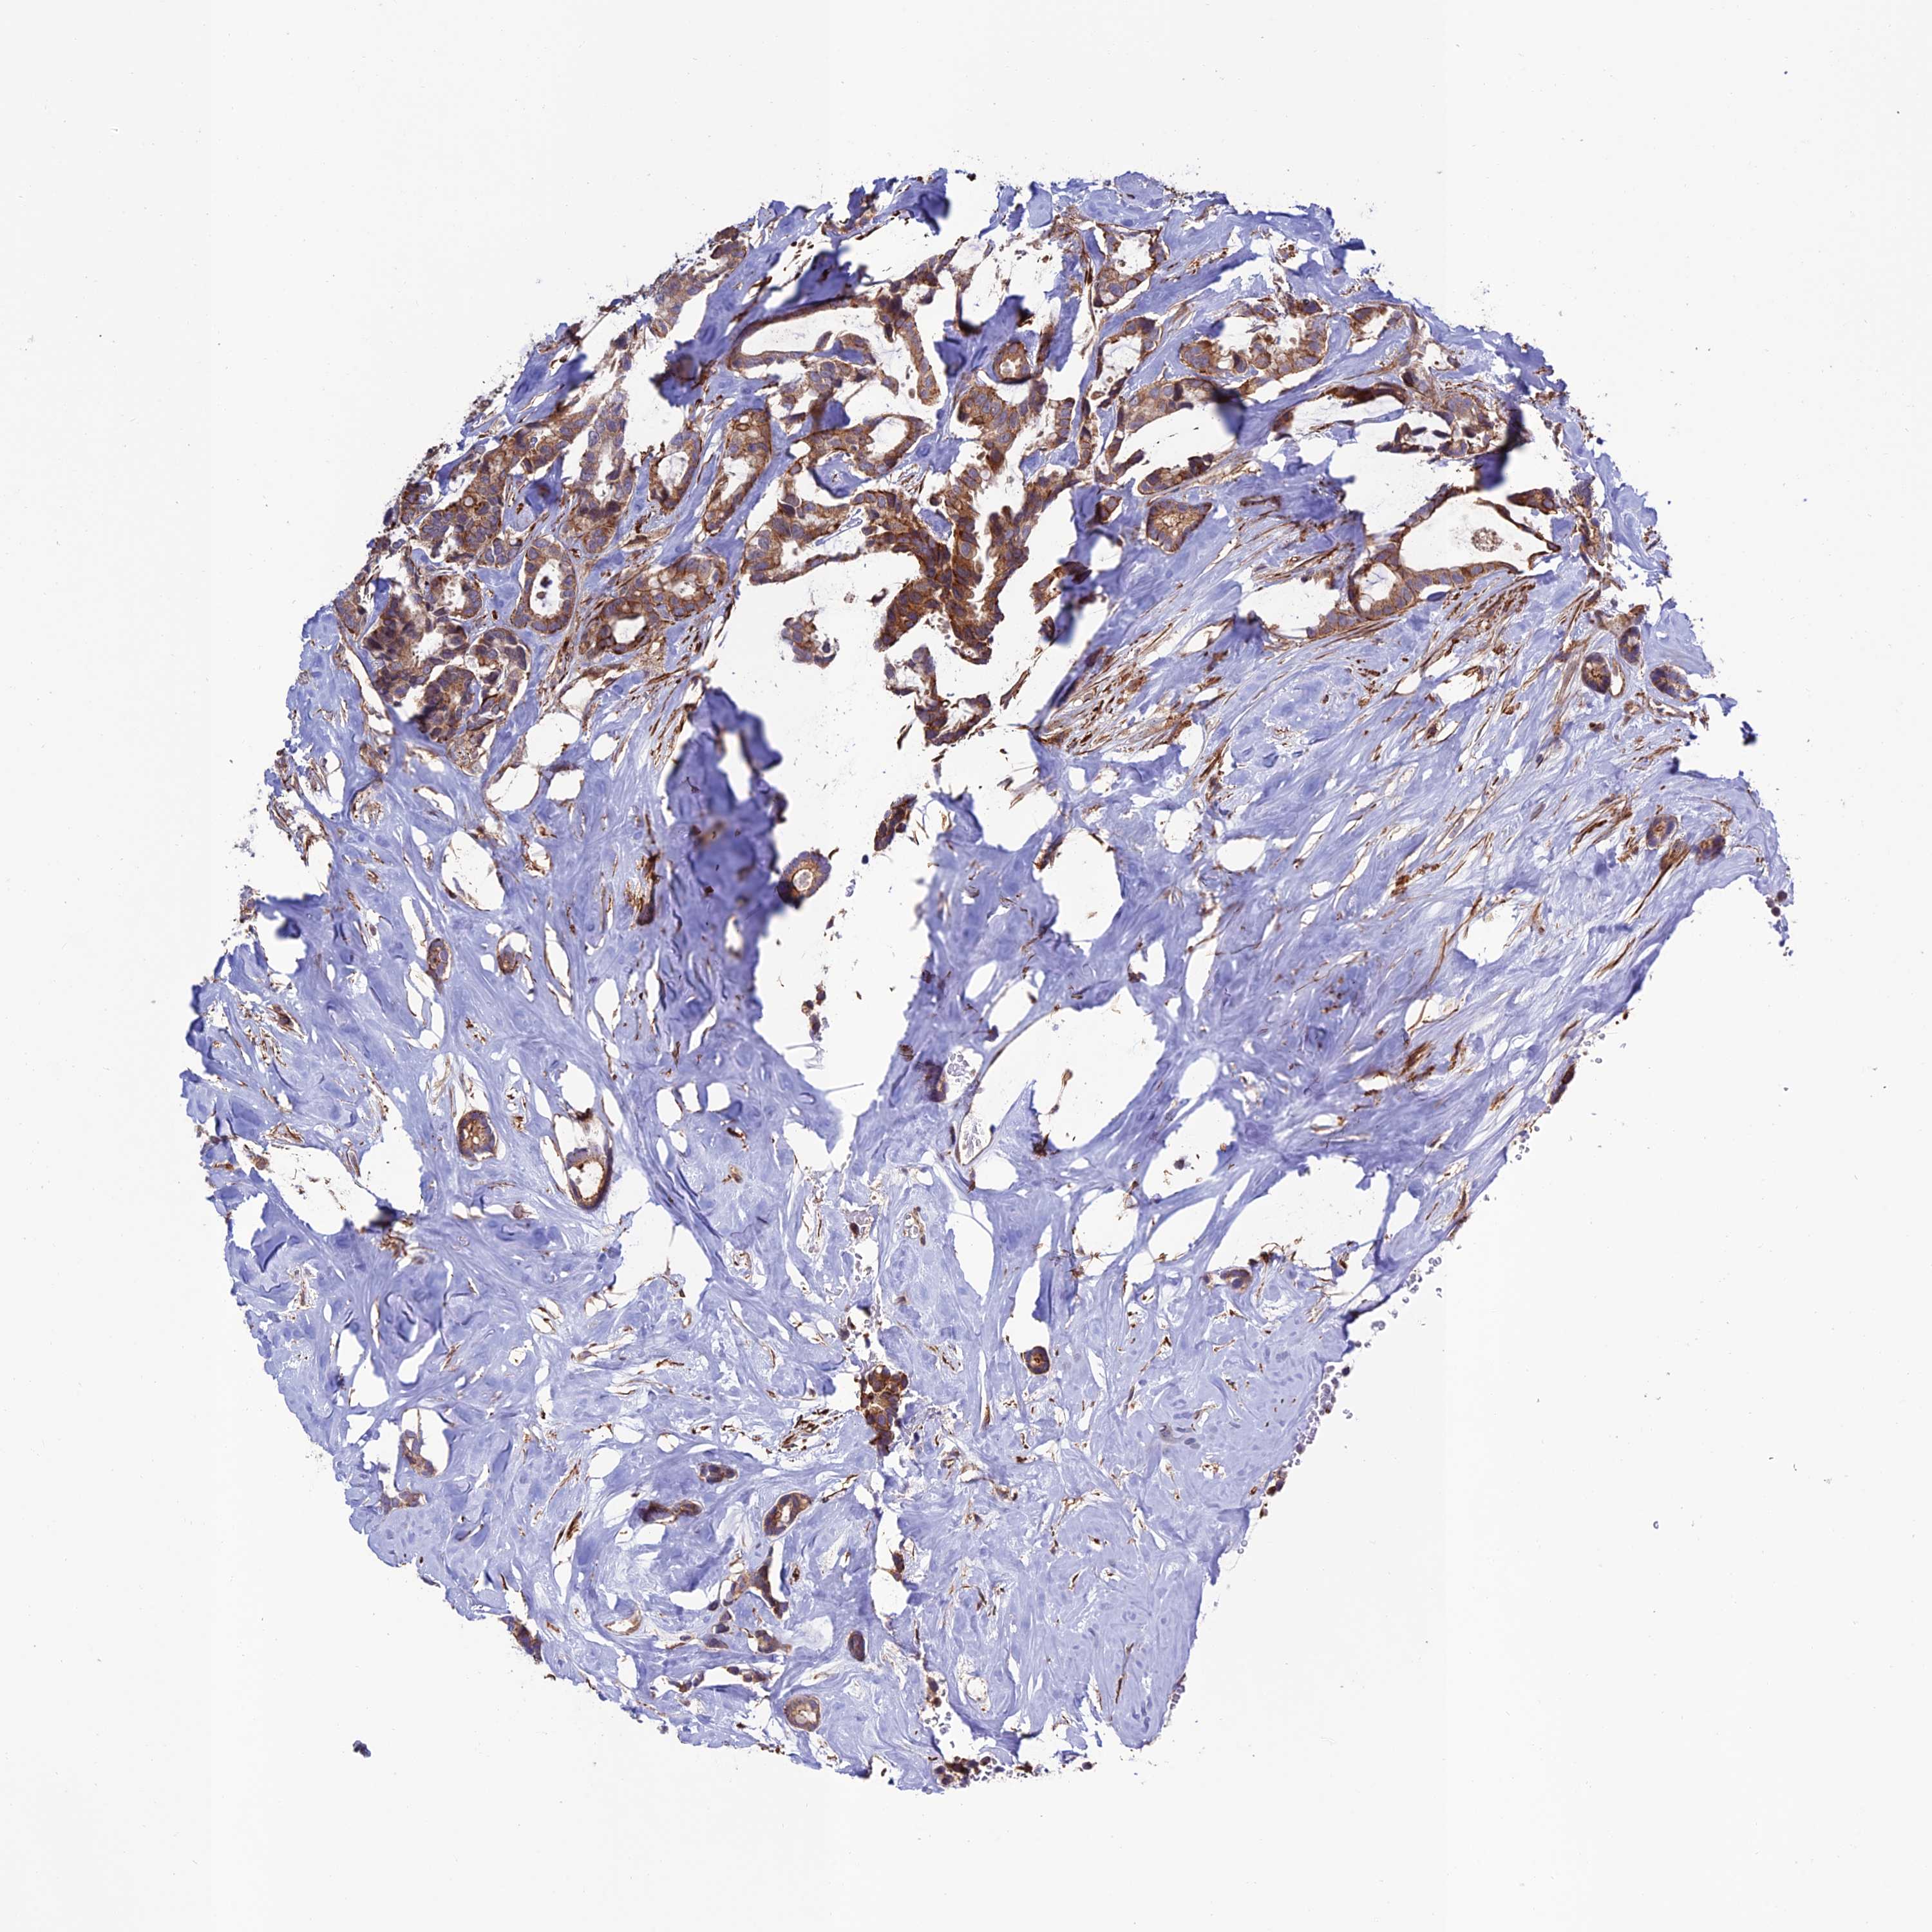

BRCA TCGA BRCA VALIDATION PROTEIN EXPRESSION

Breast cancer

Human cancer